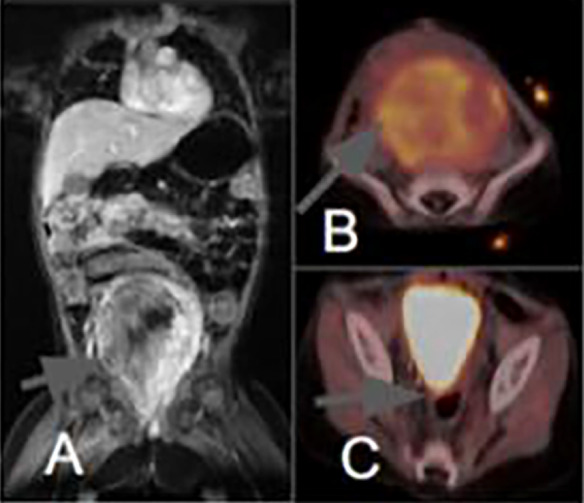

Abstract Image